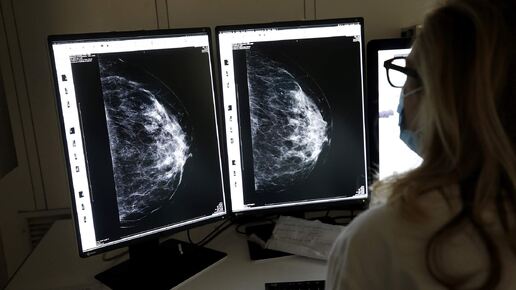

«У меня был коварный рак. Его не было видно на маммограмме. На УЗИ было образование 2,5 сантиметра, и я думала, что это киста, а у меня ведь опытные руки. МРТ показала, что на самом деле это 6 сантиметров смешанного протокового и долькового рака, ER-положительного, HER2-отрицательного». -Д-р Лиз О’Риордан

Нас учат проводить тщательное самообследование груди для выявления необычных уплотнений - возможного признака рака. Однако, как объясняет доктор Натраджан, уплотнения появляются не всегда. Из-за этого признаки могут остаться незамеченными как при самообследовании, так и на маммограммах.

«У подавляющего большинства женщин и мужчин с диагнозом рака груди клетки слипаются - это так называемые протоковые карциномы. А у Лиз, как она сказала, дольковый рак - там есть дефект в белке E-кадгерине. Он не дает клеткам слипаться, они растут в так называемых одинарных файлах. Из-за этого их сложнее обнаружить на обычных маммограммах, поскольку они не образуют солидную массу». - Д-р Рашель Натраджан

Интересное дополнение от специалистов по визуализации: Дольковая карцинома часто проявляется не как четкое образование, а как участок асимметричного уплотнения ткани, который может быть списан на естественные изменения железы.

Именно поэтому при наследственной предрасположенности или плотной ткани молочной железы часто рекомендуют МРТ как более точный метод.